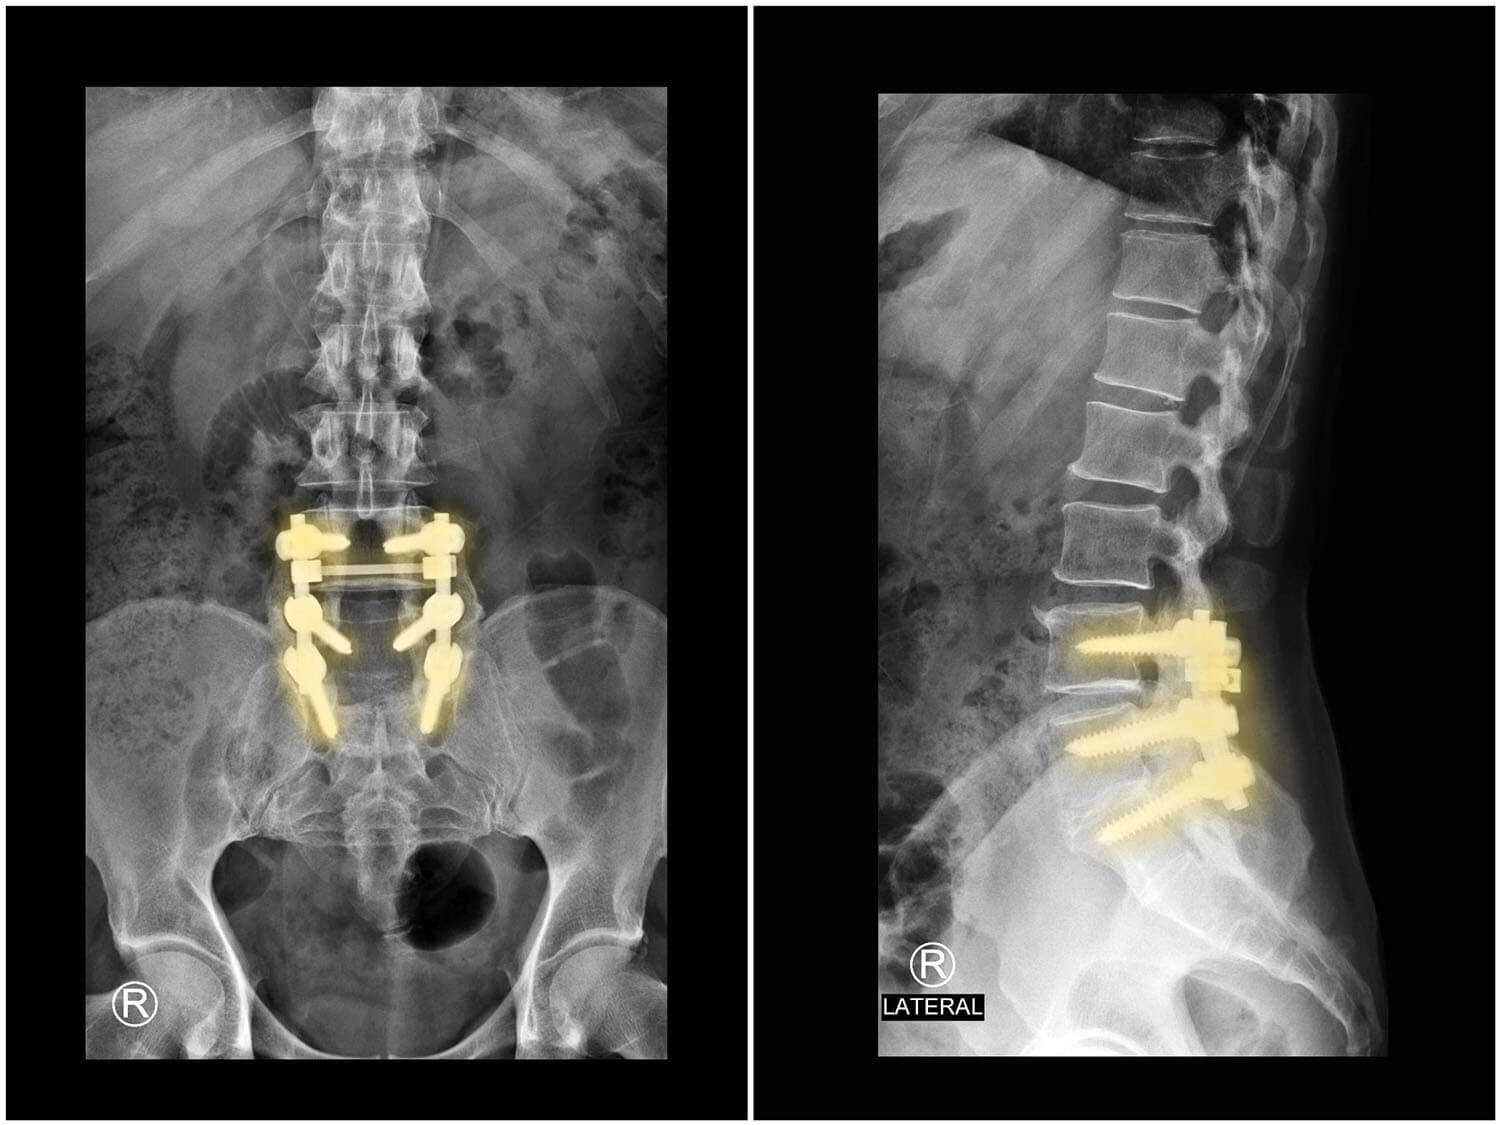

A second surgery may be recommended if imaging shows:

• Hardware failure

• Severe instability

• Persistent compression

• Structural collapse

Comparing treatment options after failed back surgery.